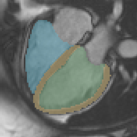

In cardiac magnetic resonance (CMR) imaging, a 3D high-resolution segmentation of the heart is essential for detailed description of its anatomical structures. However, due to the limit of acquisition duration and respiratory/cardiac motion, stacks of multi-slice 2D images are acquired in clinical routine. The segmentation of these images provides a low-resolution representation of cardiac anatomy, which may contain artefacts caused by motion. Here we propose a novel latent optimisation framework that jointly performs motion correction and super resolution for cardiac image segmentations. Given a low-resolution segmentation as input, the framework accounts for inter-slice motion in cardiac MR imaging and super-resolves the input into a high-resolution segmentation consistent with input. A multi-view loss is incorporated to leverage information from both short-axis view and long-axis view of cardiac imaging. To solve the inverse problem, iterative optimisation is performed in a latent space, which ensures the anatomical plausibility. This alleviates the need of paired low-resolution and high-resolution images for supervised learning. Experiments on two cardiac MR datasets show that the proposed framework achieves high performance, comparable to state-of-the-art super-resolution approaches and with better cross-domain generalisability and anatomical plausibility.